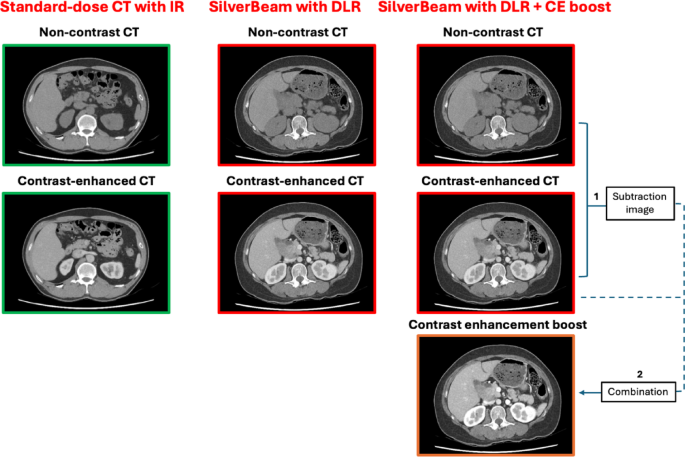

In addition, CE-boost images were generated for Silver Beam using DLR. CE-boost images were obtained by adding CE and iodinated images, which were subtracted from non-contrast and CE images during postprocessing (Fig. 1).

Study flowchart. The control group consisted of patients who underwent abdominopelvic CT at a standard dose setting with IR. In contrast, the reduced dose group included patients who underwent abdominopelvic CT at a reduced dose setting using the SilverBeam filter in combination with DLR. Additionally, in the reduced-dose CT group, CE-boost images were obtained by integrating the CE images with subtracted images. These subtracted images were generated through postprocessing by subtracting the non-contrast images from the CE images. CT computed tomography; IR iterative reconstruction; DLR deep learning reconstruction; CE contrast-enhanced.